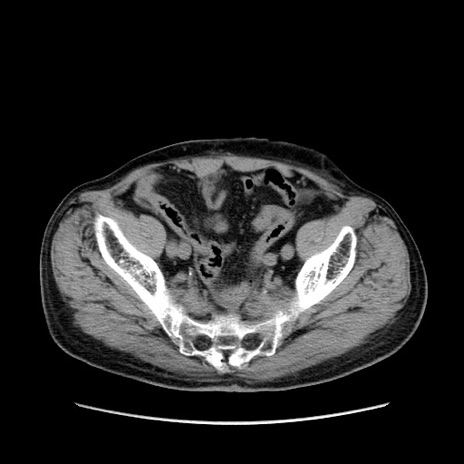

症例24(横断像)

【症例】80歳代男性

【主訴】左側腹部痛、嘔吐

【現病歴】本日早朝より左腹部に痛みあり。昼頃嘔吐認めたため、救急要請。

【既往歴】直腸癌(Mile手術)、胆摘

【身体所見】意識清明、BT 35.9℃、BP 221/93mmHg、SpO2 97%(RA) 、腹部:左ストーマ周囲に限局性の腹部膨隆あり。 膨隆部自発痛・圧痛あり・軟。

【データ】WBC 7700、CRP 0.09